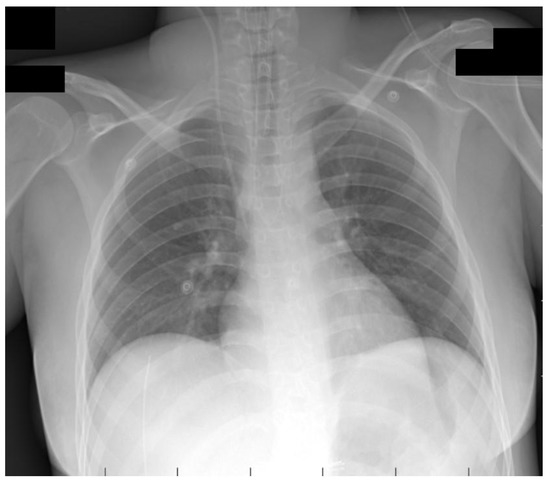

2. Case Presentation